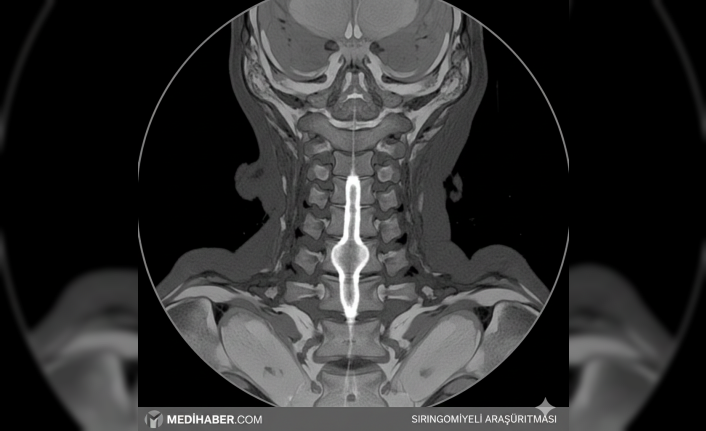

Sırtınızda garip bir yanma ya da ellerinizde bir hissizlik mi var? İnsan bazen geçer diye bekliyor ama bazen durum daha derinlerde gizli oluyor. Siringomiyeli (omurilikte kistik genişleme) işte tam böyle bir şey. Omuriliğin merkezinde biriken o sıvı, zamanla dokulara baskı yapmaya başlıyor. Aslında nadir görülür deniyor ama teşhis yöntemleri arttıkça daha çok duyuyoruz sanki.

Sıvı birikmesi sonucunda oluşan bu boşluk (siringks), sinir yollarına sinsice baskı yapar. Belki de ilk belirti sadece omuzlarda bir ağrıdır. Kim bilir? Boyun bölgesinde yoğunlaşan bu durum, sıcak ve soğuğu ayırt etmeyi zorlaştırabilir. Annem hep derdi, "Elin yanıyor da hissetmiyorsun." İşte bu tam olarak o tıbbi tablonun bir parçası galiba.

Sağlık birimlerinden alınan bilgiye göre, siringomiyeli vakalarında emar (MRG) görüntüleme hayati önem taşıyor. Hastaların nörolojik muayenelerini aksatmaması gerekiyor. Tedavi süreci hastanın klinik durumuna göre planlanıyor.